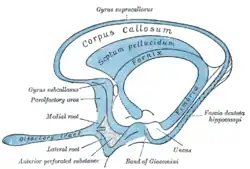

Image showing the septum pellucidum, with other structures of the rhinencephalon also shown | |

The septum pellucidum (Latin for "translucent wall") is a thin, triangular, vertical double membrane separating the anterior horns of the left and right lateral ventricles of the brain. It runs as a sheet from the corpus callosum down to the fornix.

The septum pellucidum is located in the septal area in the midline of the brain between the two cerebral hemispheres. The septal area is also the location of the septal nuclei. It is attached to the lower part of the corpus callosum, the large collection of nerve fibers that connect the two cerebral hemispheres. It is attached to the front forward part of the fornix. The lateral ventricles sit on either side of the septum.